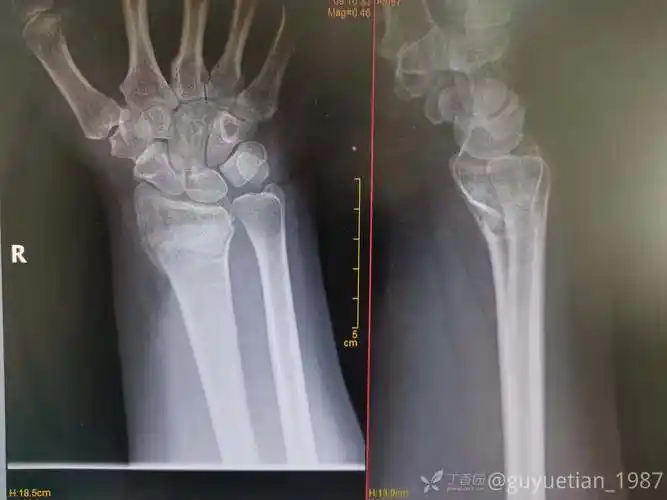

barton骨折合并掌骨骨折非手术治疗

35岁摔倒后手腕巴顿骨折及时复位才能效果满意

巴顿骨折

掌侧barton骨折小夹板保守治疗

barton骨折的临床表现